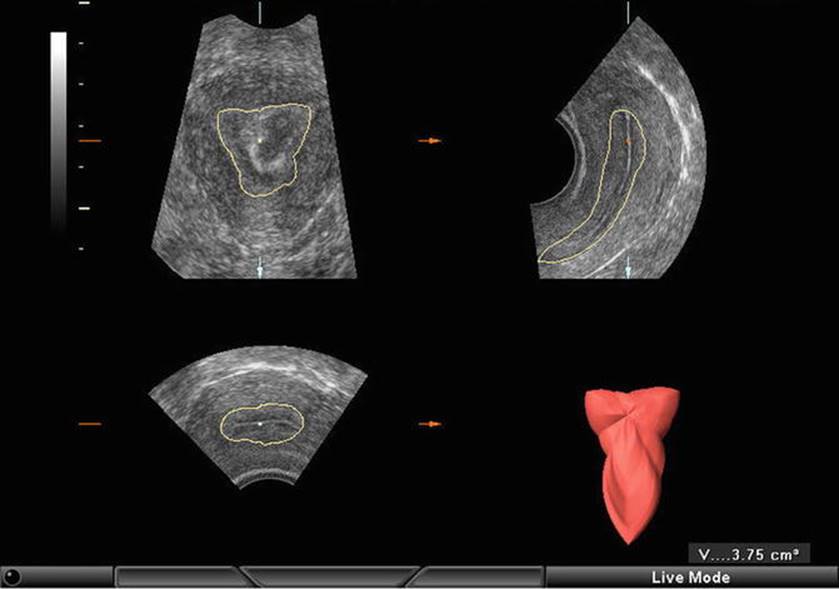

Endometrial Volume (Fig. 2.19)

Fig. 2.19

Endometrial volume evaluation

The minimum endometrial volume, which is associated with pregnancy, is 1.59 mL when calculated by 3D ultrasound, but most pregnancies occur in volumes of 2–13 mL. The calculation of endometrial volume is particularly useful in cases of synechiae, adenomyosis, and uterine anomalies to predict the outcome of treatment.

Endometrial and subendometrial volume increase rapidly during the follicular phase and then remain almost unchanged during the luteal phase [36].